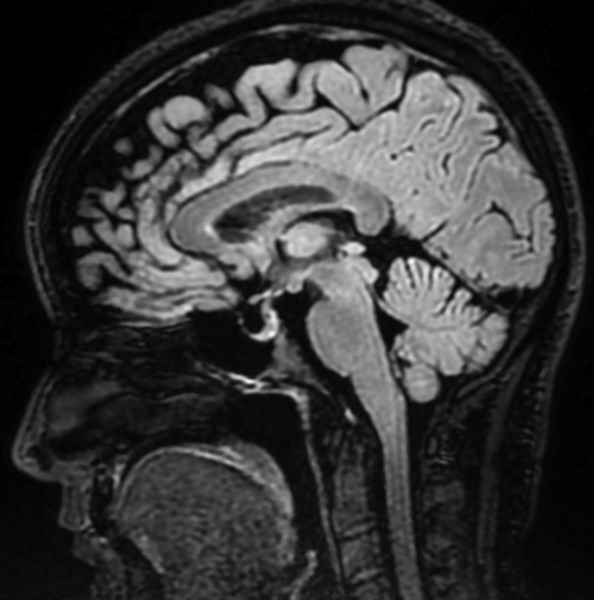

W badaniu neurologicznym wykonanym przy przyjęciu na oddział nie stwierdzono odchyleń od stanu prawidłowego, poza zgłaszanym przez pacjentkę dwojeniem przy spojrzeniu na wprost i w prawo. Wykonano rezonans magnetyczny (MR) głowy z kontrastem, który wykazał objaw częściowo pustego siodła tureckiego (ryc. 1). W MR odcinka szyjnego kręgosłupa uwidoczniono cechy umiarkowanej spondylozy szyjnej, bez zmian pourazowych. W rezonansie magnetycznym oczodołów wykazano natomiast cechy nadciśnienia śródczaszkowego pod postacią zwiększonej ilości płynu w pochewkach nerwów wzrokowych oraz obrzęku tarcz, z poszerzeniem zbiornika nadsiodłowego (ryc. 2, 3).

Rycina 2. Rezonans magnetyczny oczodołów STIR w płaszczyznach czołowych – zwiększona ilość płynu w pochewkach nerwów wzrokowych